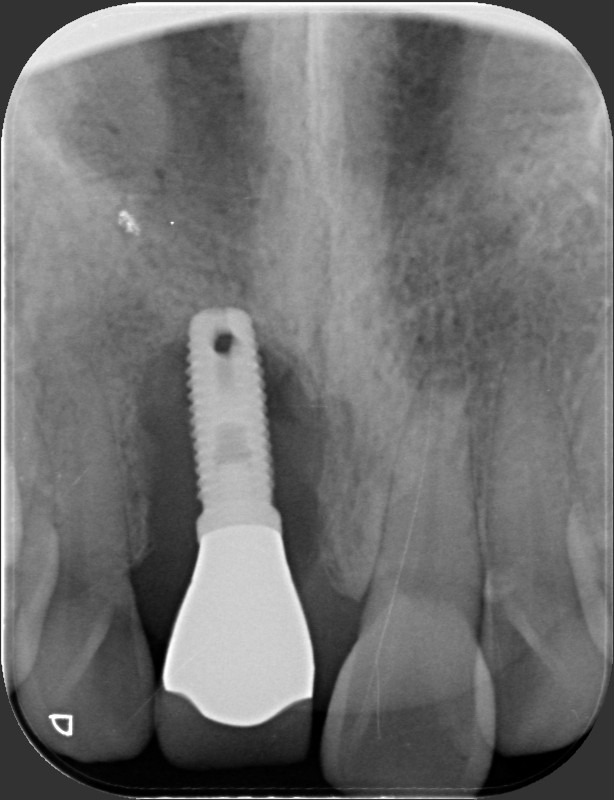

王柏凱醫師說明,所謂植體周圍炎指的是細菌在人工植體周圍產生的發炎現象,若不及早處理,最終可能導致骨質流失與植體鬆動。要想避免植體周圍炎,術後口腔清潔與戒除不良習慣是防範關鍵。傳統的全口植牙重建通常需在上顎植入八顆、下顎植入六顆植體,以支撐整副假牙;雖然這種方法在條件許可下能恢復大部分咀嚼功能,但植體數量一多,每個植體周圍都可能成為細菌侵襲的據點,增添清潔難度。

如果植體後方位置過深,加上牙齦萎縮、螺紋暴露,就更容易堆積牙菌斑,植體結構恐淪為「細菌的溜滑梯」,使炎症沿著螺紋向下蔓延。對有牙齦萎縮或清潔不佳的患者而言,植體周圍炎的威脅恐將增加。相較之下,All-On-4只需在上顎植入五顆、下顎植入四顆植體(或稍作調整),即能支撐整座牙橋。植體數量雖減少,但並不代表就能高枕無憂;真正決定植牙長期穩定的,仍在於患者的術後保養。